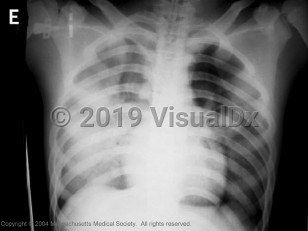

Atypical presentations of avian influenza have been reported. Patients have developed nausea, vomiting, and diarrhea preceding acute respiratory failure. Progression to acute respiratory distress syndrome (ARDS) and respiratory failure is common. Complications have included bacterial sepsis, pulmonary hemorrhage, and multi-organ failure. The mortality rate of hospitalized patients has been high due to progressive respiratory failure.